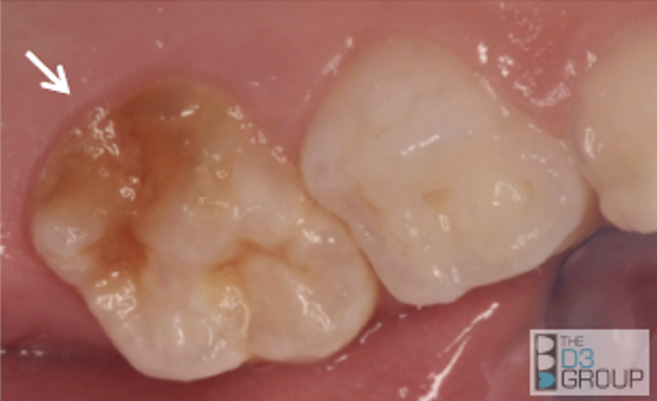

Clinical examples of MH are provided in Figure 1.

6-year molars. Left: demarcated opacity, brown in color, breakdown occurred during eruption. Considered extremely severe involvement. Right: sporadic distribution of hypomineralization. The molar on the right-side displays severe hypomineralization with decay. The molar on the left side shows only mild hypomineralization (arrows). Note that neither of the 2-year molars are involved, suggesting that plaque-related dental caries is not the cause.